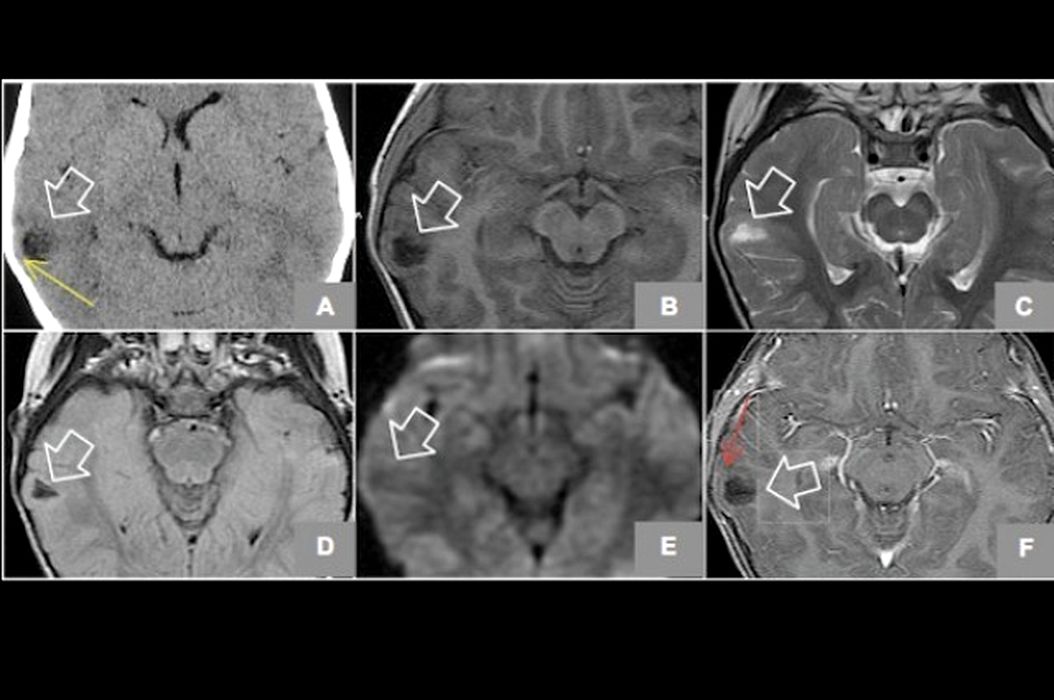

Oamenii credeau că e posedată, pentru că nu se putea opri din râs. Ce au aflat medicii? (FOTO)

O fetiţă de 6 ani din Bolivia avea crize incontrolabile de râs. Comportamentul ei ciudat era considerat uneori proastă-creştere, răsfăţ, nebunie, deşii unii bănuiau chiar că micuţa este posedată de Diavol.